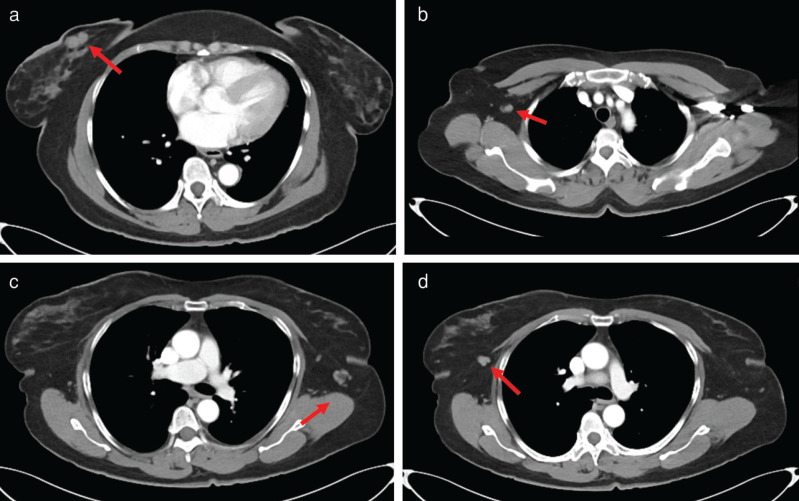

Rosai-Dorfman disease (RDD) is a self-limited, idiopathic, non-neoplastic disorder characterized by the proliferation of phagocytic histiocytes, which can mimic malignant lymphoproliferative disease. Cases of RDD most commonly present as bilateral painless cervical lymphadenopathy, with lesser involvement of the axilla, inguinal, and mediastinal lymph nodes. We present the case of a 62-year-old woman with a history of endometrial serous carcinoma who underwent evaluation at a dedicated breast imaging department after positron emission tomography/computed tomography (PET/CT) revealed breast masses and axillary nodes with increased uptake of fluorodeoxyglucose (FDG). Upon clinical examination, she had bilateral palpable lumps in both breasts and axillae. Subsequent dedicated breast imaging with bilateral diagnostic mammography with tomosynthesis and bilateral complete breast ultrasound were suspicious for malignancy detecting bilateral breast masses and axillary lymphadenopathy corresponding to the FDG-avid findings on PET/CT. Ultrasound-guided core needle biopsies, however, revealed a diagnosis of RDD. This case highlights the unique characteristics of RDD with an atypical clinical presentation suspicious for breast cancer both clinically and radiologically.